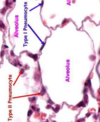

cells in alveoli epithelium

1. type 1 alveolocytes = v thin squamous

2. type 2 = cuboidal to prod surfactant (keep surface bet cells + air moist)

3. macrophage to phagocytose tiny foreign particles/infectious agents past nasal + escalator -> alveoli

alveolocytes = pneumocytes